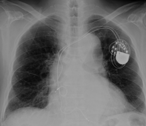

Dramatic improvement of left ventricular function after switching the ventricular pacing site from the right ventricular apex to the left ventricular free wall via a left mini thoracotomy: a case report

Masahiro Tsutsui and others

Journal of Surgical Case Reports, Volume 2019, Issue 5, May 2019, rjz155, https://doi.org/10.1093/jscr/rjz155